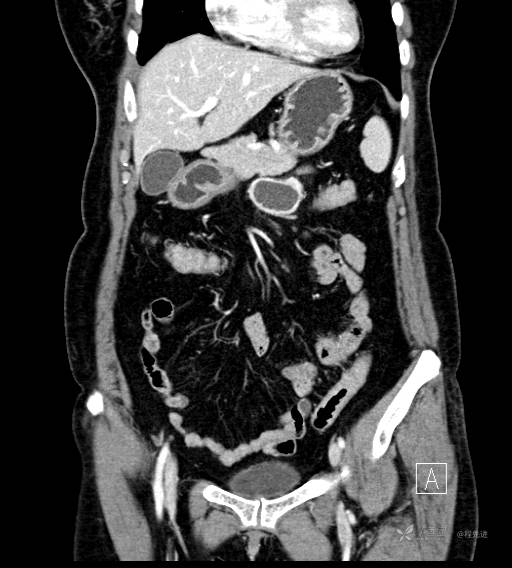

CT增强静脉期

CT增强冠状位重建